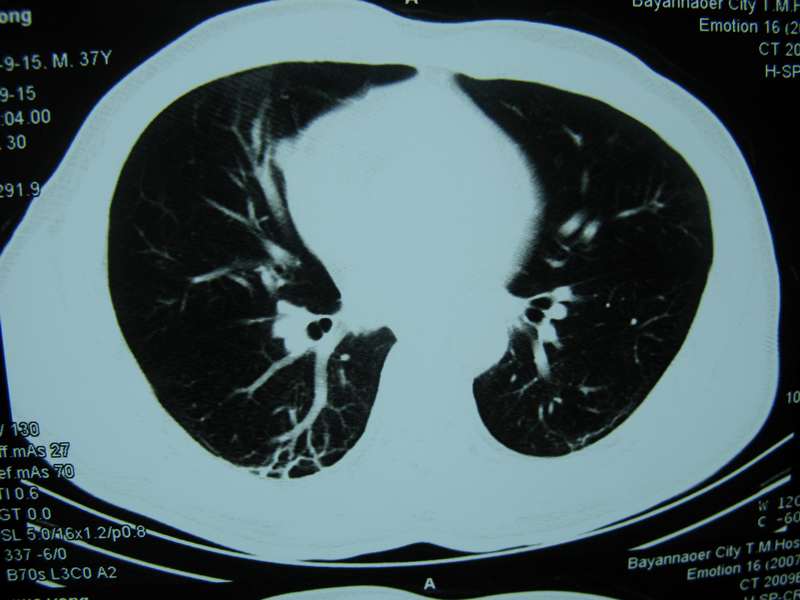

男,37岁,主述胸疼厉害,无咳嗽,无发热,血象也不高,病灶内ct值脂肪密度,右侧胸腔内少量积液,同道们考虑什么?谢谢!

两肺下叶基底段纤维灶,右肺下叶基底背侧相应胸膜肥厚,右肺中叶内侧段部分不张。前中下纵隔团块状脂肪影,随访除外胸腺脂肪瘤。

不除外膈疝。